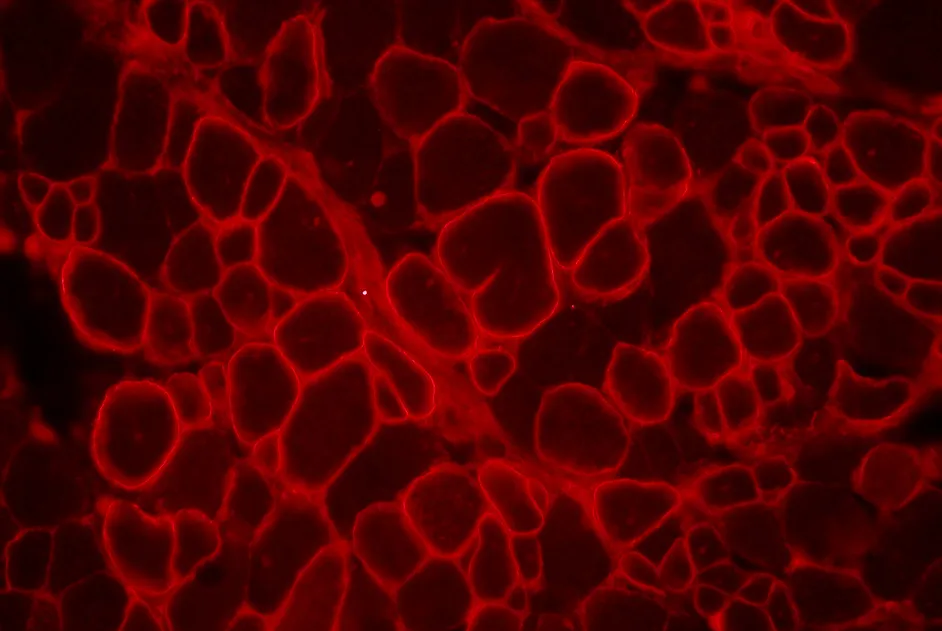

Maladie de Pompe : des doses plus fortes de Myozyme® chez l’enfant ?

Les résultats d’une étude néerlandaise sont favorables à une enzymothérapie plus soutenue dans la forme infantile de glycogénose de type II.